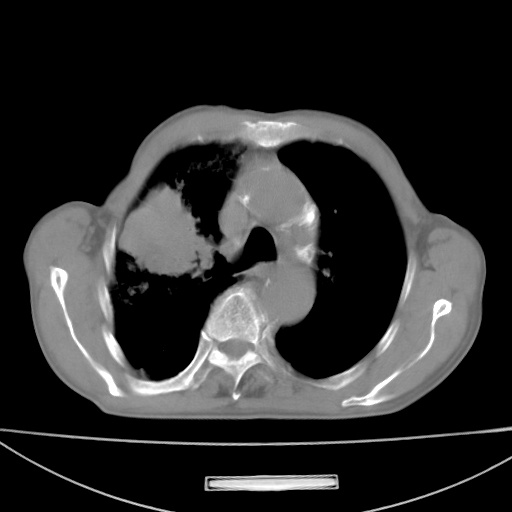

标题: CT13796:请会诊右上费病变!

患者男80岁,反复咳嗽多年,咳喘伴咯血1月

右上肺周围型肺癌伴肺门淋巴结转移.右上肺继发型肺结核.

右上肺周围型肺癌伴肺门淋巴结转移

右肺上叶占位性病变,考虑周围型肺癌,肺门淋巴结转移。要是能提供更多的临床资料就好了,以供鉴别诊断。

右肺尖周围型肺癌伴肺门淋巴结肿大

右肺上叶占位性病变,考虑周围型肺癌,肺门淋巴结转移。

右上肺周围型肺癌伴肺门、纵膈淋巴结转移

考虑为:右肺上叶肺癌伴阻塞性肺炎、右肺门及纵膈淋巴结转移。